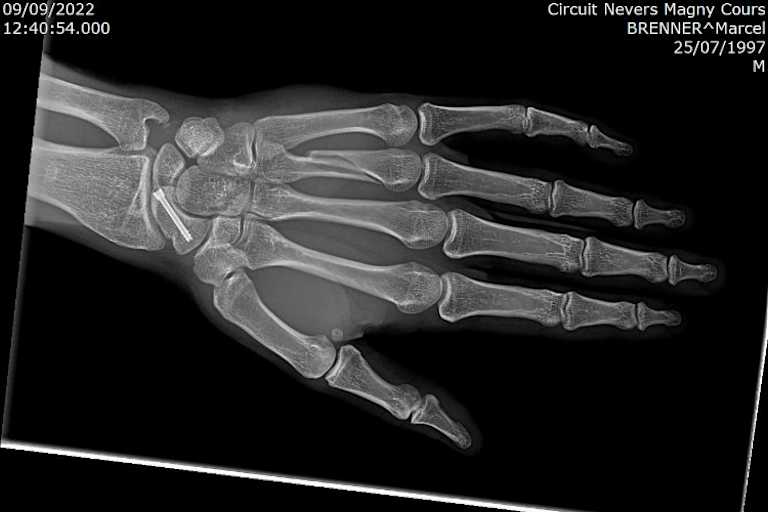

Dienstagvormittag wurde Marcel Brenner (VFT Yamaha) im Engeriedspital in Bern am gebrochenen vierten Mittelhandknochen links operiert. Beim nächsten Supersport-WM-Rennen in Barcelona will er wieder dabei sein.

Er reiste umgehend nach Hause in die Schweiz und wurde beim Arzt seines Vertrauens vorstellig. Am Dienstagmorgen wurde Brenner im Engeriedspital in Bern am gebrochenen vierten Mittelhandknochen links operiert. "Sie haben mir eine Platte mit zwei Schrauben eingesetzt", erzählte Marcel SPEEDWEEK.com. "Jetzt geht es zehn Tage bis Barcelona. Das ist eine kurze Zeit, aber ich hoffe, dass ich relativ schnell wenig Schmerzen habe und dort fahren kann. Ich werde auf jeden Fall anreisen, dann müssen die Ärzte der Clinica Mobile entscheiden, ob ich fit bin oder nicht. Ich werde alles geben, dass ich fahren kann. Barcelona zählt zu meinen besten Strecken, weil ich sie aus der CEV sehr gut kenne."